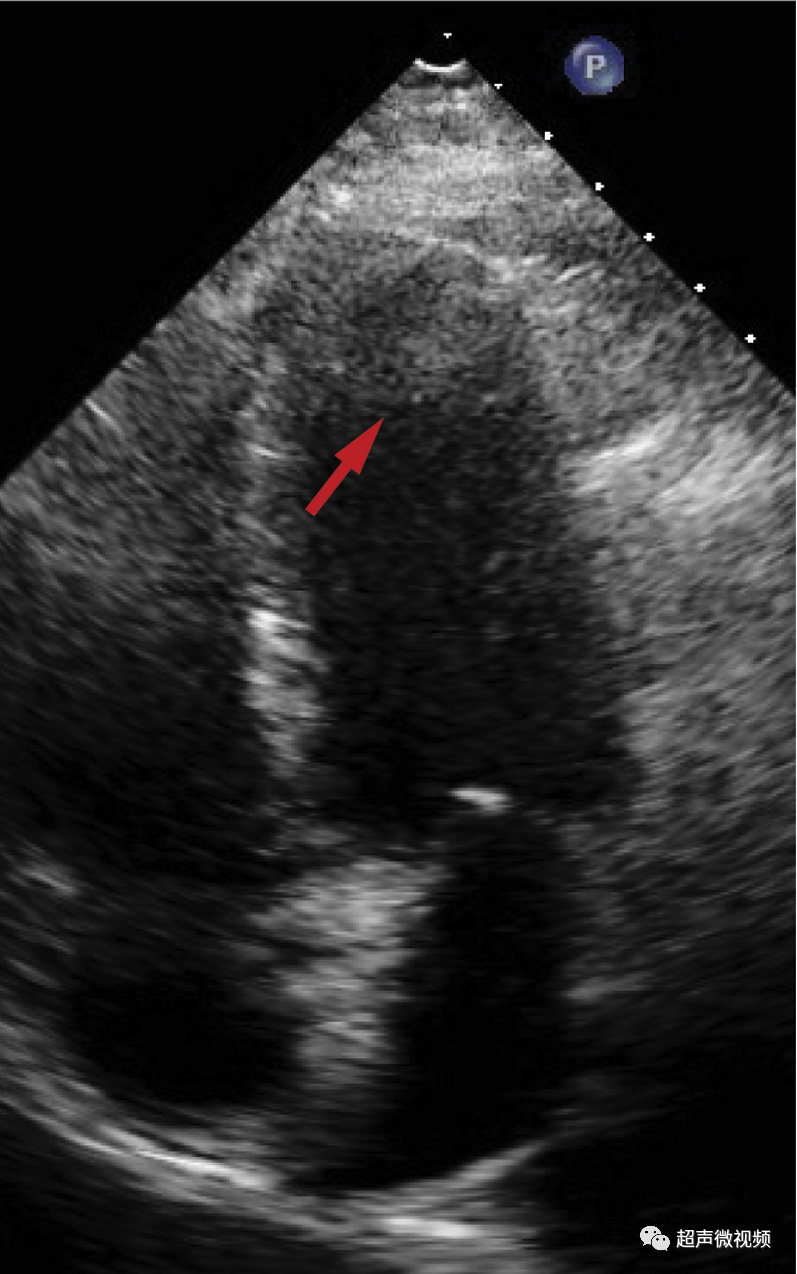

7、近场杂波

由于探头换能器本身的高振幅振荡,近场结构有时会被遮蔽,造成所谓的近场杂波。这在怀疑有心尖室血栓的病例中尤其重要(图7,视频10)。谐波成像的引入和换能器设计技术的进步已经减少了这种伪影的发生。

图7 心尖四腔视图中的近场杂波(箭头),疑似心尖血栓。(视频10)显示正常的心尖心肌动力学,杂乱回波和心肌运动之间没有关系。